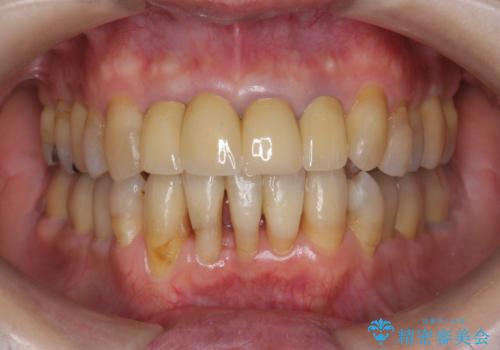

矯正を含む全顎治療